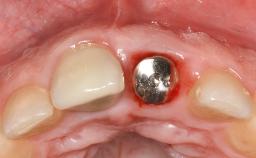

Resective Surgical Treatment of Peri-Implantitis Including Implantoplasty

In this case, Myroslav Solonko, Ignacio Sanz Sánchez and Mariano Sanz present a treatment that aims to eliminate exposed implant threads by modifying the implant surface, converting a moderately-rough surface into a smooth surface.

A 63-year-old male patient was referred to the post-graduate periodontal clinic of the Complutense University of Madrid for the treatment of peri-implantitis. According to the patient’s record, all his maxillary teeth had been extracted ten years previously due to severe periodontitis, and a full-mouth implant-supported restoration on eight implants was placed. No supportive periodontal therapy was provided apart from occasional check-ups by the restorative dentist.